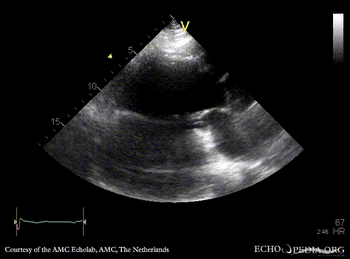

Large pseudoaneurysm of posterior wall

A3CH: large pseudoaneurysm of posterior wall, spontaneous echocontrast A3CH: Color Doppler, severe mitral regurgitation